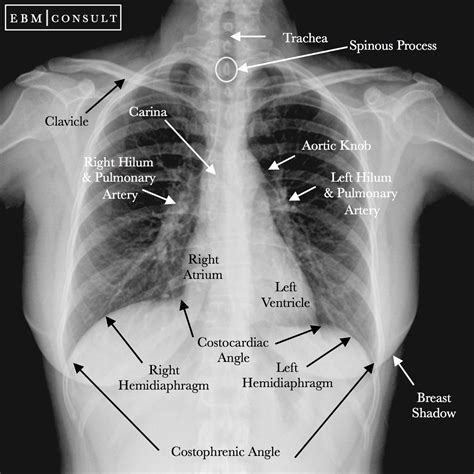

A normal chest X-ray shows a clear and symmetrical image of the lungs, heart, and chest wall. The lungs should appear dark and free of any abnormalities, while the heart should be of normal size and shape. The chest wall and ribs should also appear normal, with no signs of fractures or other injuries. It is essential to note that a normal chest X-ray does not necessarily rule out all possible health issues, as some conditions may not be visible on an X-ray.

Here are five ways to interpret a normal chest X-ray: * Lung Fields: The lung fields should be clear and free of any abnormalities, such as nodules, masses, or infiltrates. The lungs should also be of equal size and shape. * Heart Size and Shape: The heart should be of normal size and shape, with no signs of enlargement or abnormality. The cardiothoracic ratio, which is the ratio of the heart size to the chest size, should be within normal limits. * Chest Wall and Ribs: The chest wall and ribs should appear normal, with no signs of fractures, deformities, or other injuries. * Diaphragm and Mediastinum: The diaphragm and mediastinum should appear normal, with no signs of abnormalities, such as masses or infiltrates. * Pleura and Airways: The pleura and airways should appear normal, with no signs of abnormalities, such as pleural effusions or airway diseases.

A normal chest X-ray can reveal a lot about a person’s health, including: * Lung Health: A normal chest X-ray can indicate that the lungs are healthy and free of diseases, such as pneumonia or lung cancer. * Heart Health: A normal chest X-ray can indicate that the heart is healthy and of normal size and shape, which can rule out conditions such as heart failure or cardiomegaly. * Chest Wall and Rib Health: A normal chest X-ray can indicate that the chest wall and ribs are healthy and free of injuries or deformities. * Diaphragm and Mediastinum Health: A normal chest X-ray can indicate that the diaphragm and mediastinum are healthy and free of abnormalities.